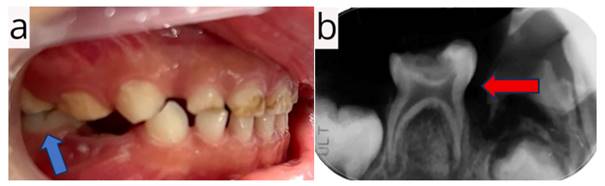

Durante la consulta, la niña mostró timidez y poca colaboración. El examen clínico reveló una lesión cariosa extensa y profunda con afectación pulpar, inflamación de la encía marginal y presencia de una fístula de origen dental en la pieza 85 (figura 1A). El estudio radiográfico confirmó una lesión cariosa coronaria amplia y profunda con compromiso pulpar, además de un proceso osteolítico periapical e interradicular, acompañado de osteítis condensante circundante (figura 1B). El diagnóstico definitivo fue necrosis pulpar con periodontitis apical crónica. Se determinó como plan de tratamiento realizar una pulpectomía utilizando un sistema rotatorio continuo para garantizar la eliminación completa del tejido necrótico y preservar la integridad del diente.

Figura 1 Examen inicial clínico y radiográfico de la pieza 85. A) Fotografía clínica zonal. B) Radiografía periapical antes del tratamiento.